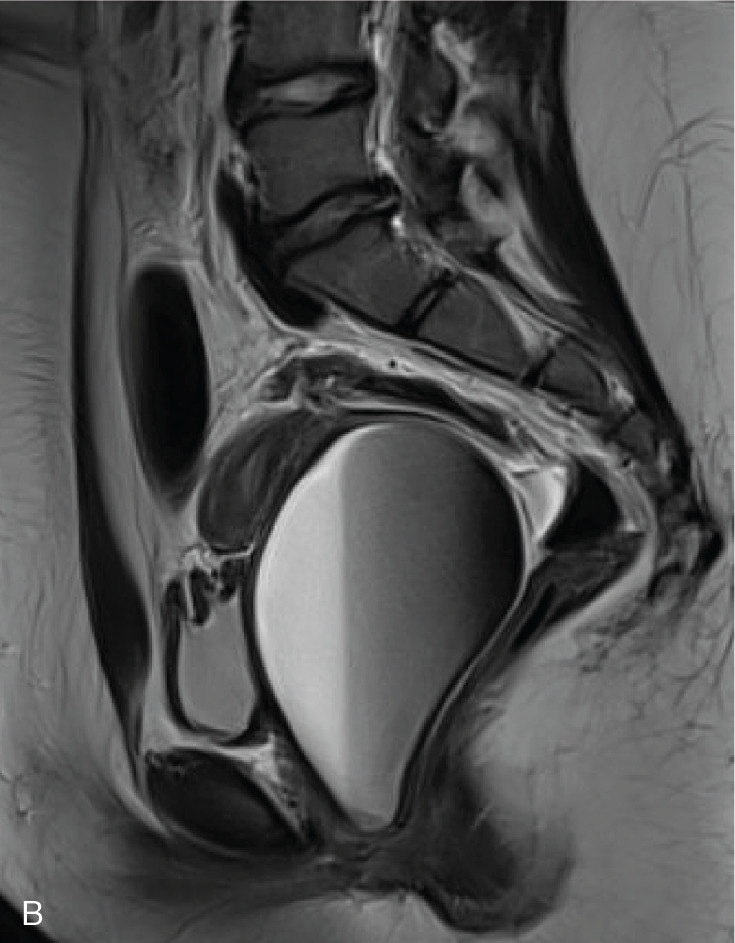

Hematocolpos, characterized by the accumulation of menstrual blood in the vagina, is a rare condition often misdiagnosed due to its uncommon occurrence and non-specific symptoms. Main causes include imperforate hymen, obstructed hemivagina with ipsilateral renal anomaly (OHVIRA), congenital lower vaginal atresia, and complete transverse vaginal septum. Without early diagnosis and treatment, complications such as tubal adhesion, pelvic endometriosis, and infertility can occur. This article reviews the differential diagnosis and treatment of hematocolpos.